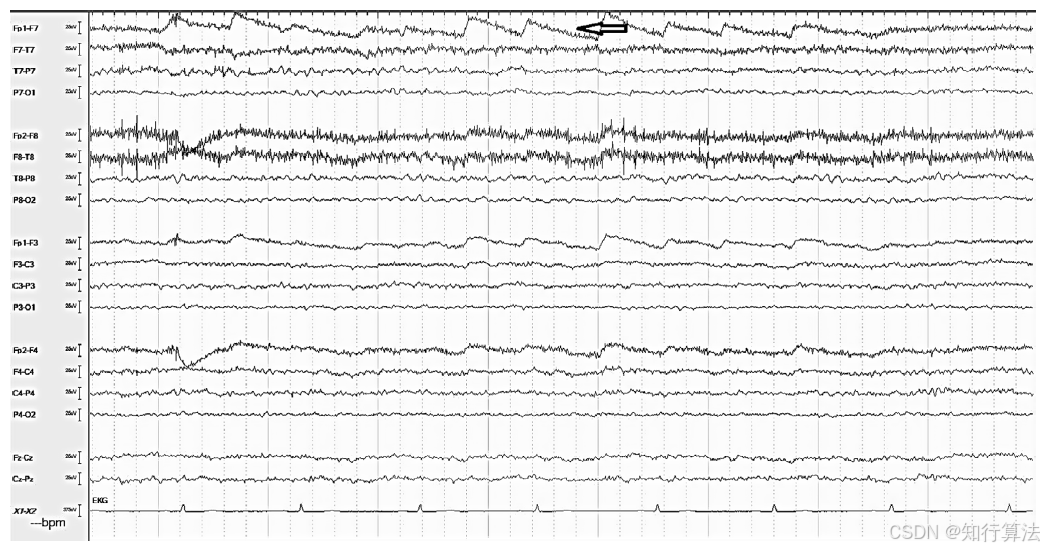

波形特征:形态多变,但仅出现在包含该电极的导联(无电场扩散)。可表现为尖波、周期性或节律性波(图1)。60 Hz干扰可使多个导联出现密集的细波,模拟背景活动(图2)。

图1:T8 导联尖波样周期性电极伪差

图2:P7 电极处有“爆裂”伪迹。另外请注意心率不齐。